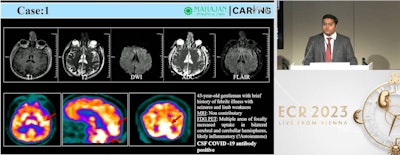

In a presentation of cases, Seniaray showed images of a 43-year-old patient who reported a brief history of febrile illness with seizures and limb weakness. The MRI scan was noncontributory, while the PET/CT scan showed increased F-18 FDG radiotracer uptake in the bilateral cerebral and cerebellar brain hemispheres, likely inflammatory, he said.

Moreover, the patient was put on immunomodulatory treatment and a follow-up FDG PET/CT scan one week later showed resolution of the hypermetabolism, he said.